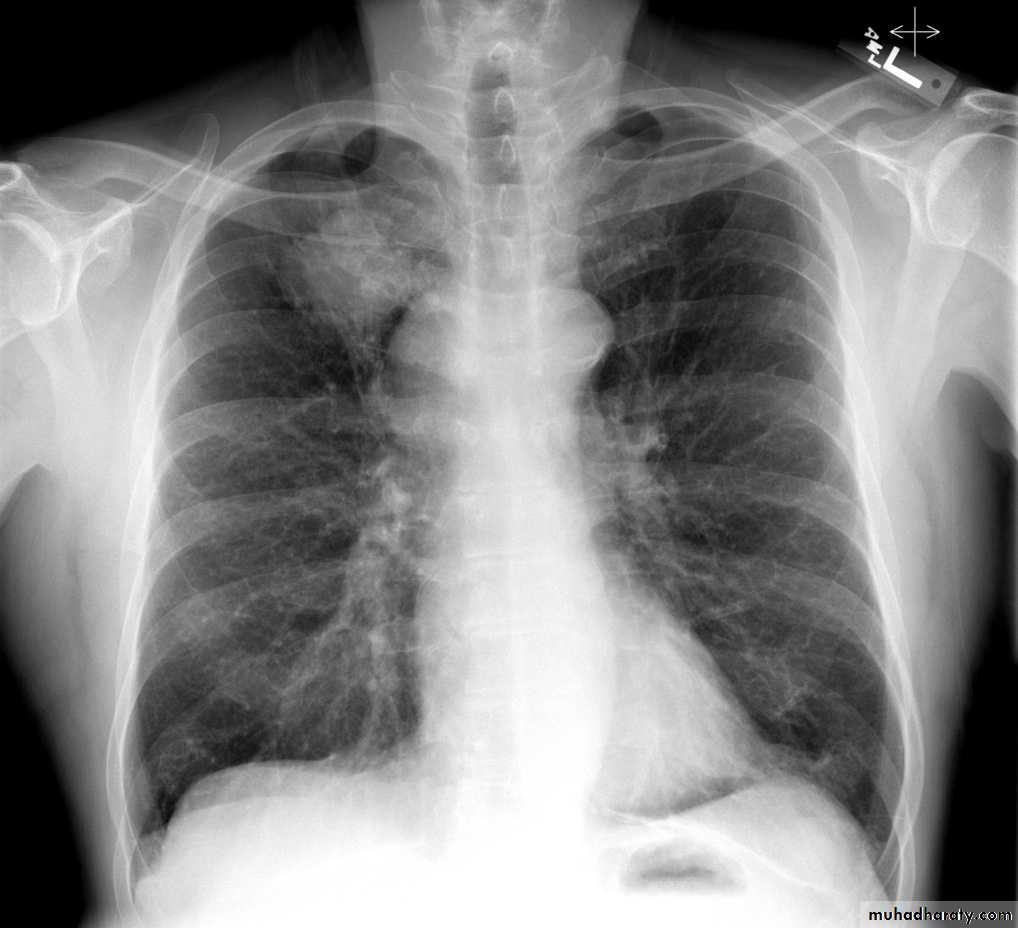

Emphysema

47.Emphyzema